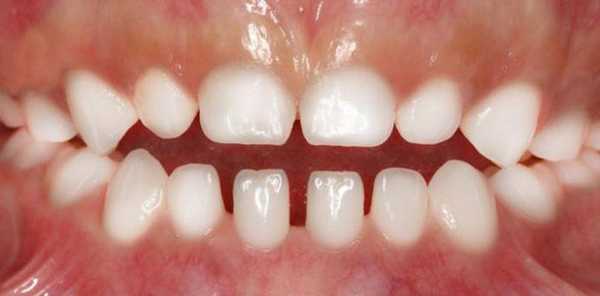

В два годика у малыша резцы располагаются рядом друг с другом, верхние резцы немного перекрывают нижние (при смыкании зубов), потертости на эмали не обнаруживается. Это при правильном развитии зубочелюстной системы.

Для прикуса, находящегося на этапе формирования, характерны следующие особенности:

- целостность эмали и отсутствием признаков ее стирания;

- тесное расположение друг к другу, с образованием минимального межзубного промежутка;

- отсутствие перекрытия нижнего ряда зубов верхним во время смыкания;

- отсутствие свободного места за последними молярами .